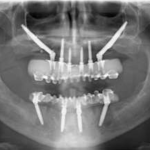

Tecnica Hybrid Zygoma per la riabilitazione di un mascellare atrofico Premium

Un mascellare superiore edentulo e fortemente atrofico è stato riabilitato con l’ausilio di impianti zigomatici. Nello specifico è stata applicata la tecnica Hybrid, che prevede l’inserimento di una fixture zigomatica per lato nelle regioni posteriori e di due o più impianti tradizionali nella premaxilla. Per la realizzazione di questo caso sono stati impiegati impianti zigomatici caratterizzati da un nuovo, particolare design, con una superficie piatta a livello vestibolare che migliora la guarigione dei tessuti molli della regione malare, prevenendo eventuali decubiti della mucosa.